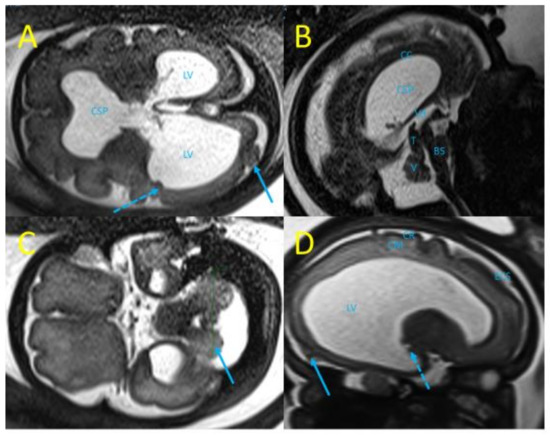

3. Case Report